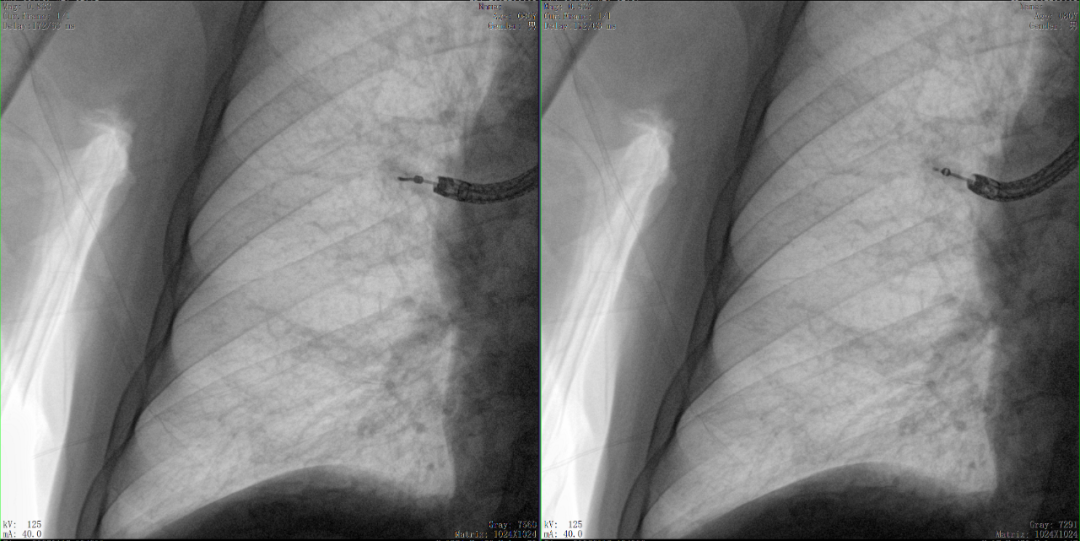

病例3:超聲支氣管鏡下肺活檢(80歲)

三維C形臂還可以創(chuàng)新性地應(yīng)用在呼吸介入領(lǐng)域。例如,在經(jīng)皮穿刺或經(jīng)支氣管鏡肺結(jié)節(jié)活檢、定位、消融等場景中,用于確認工具是否到達病灶、消融范圍是否完全覆蓋病灶等。

二維影像無法準確判斷工具是否到達病灶

三維各切面影像都顯示工具達到病灶內(nèi)